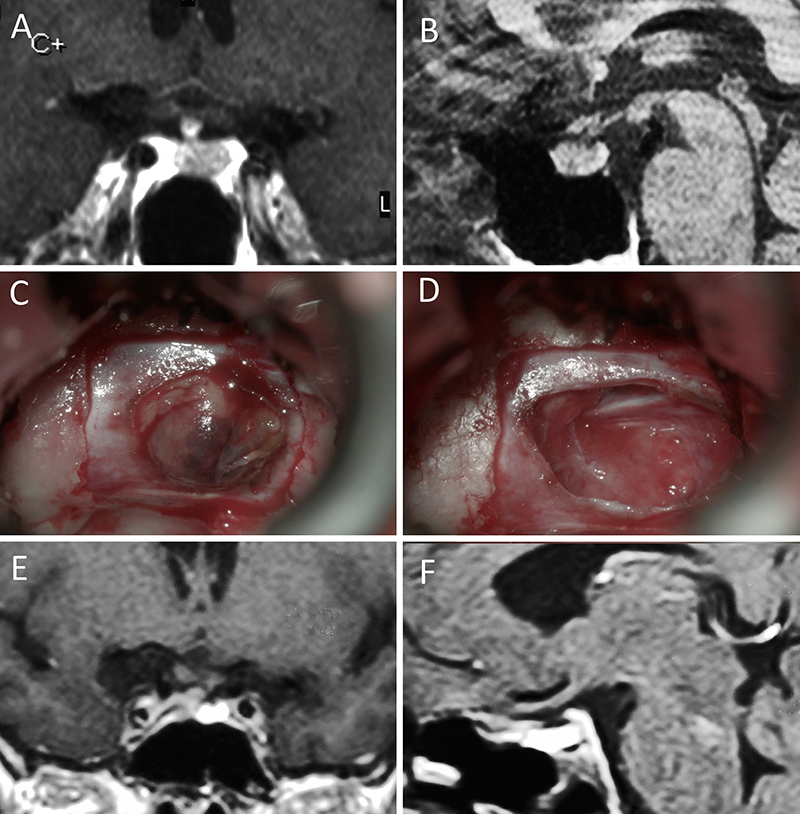

Figura 1: Macroadenoma no funcionante en mujer de 65 año s. Se decidió la cirugía tras evidenciarse crecimiento en los controles. Evolucionó favorablemente desde el punto de vista clínico-radiológico. A-B: RM preoperatoria; C-D: intraoperatorio; E-F: RM postoperatoria.